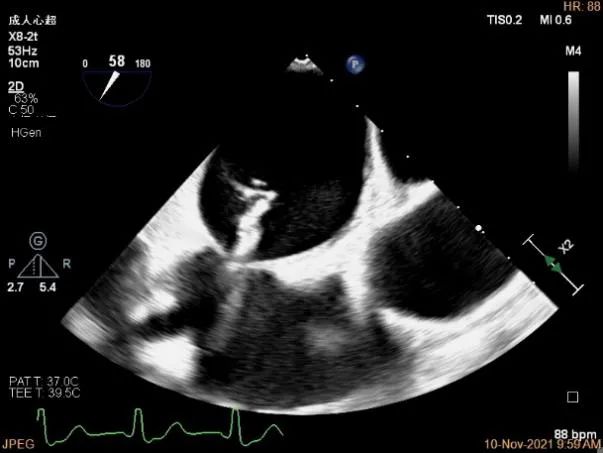

3D MV View:P1区瓣体瘤形成并中央型破裂孔,脱垂从P1到P2区,脱垂宽度13.1mm,破裂孔大小4.1×5.6mm

TEE Bicom view:主要病变区域为P1区,瓣叶中部可见连续性中断